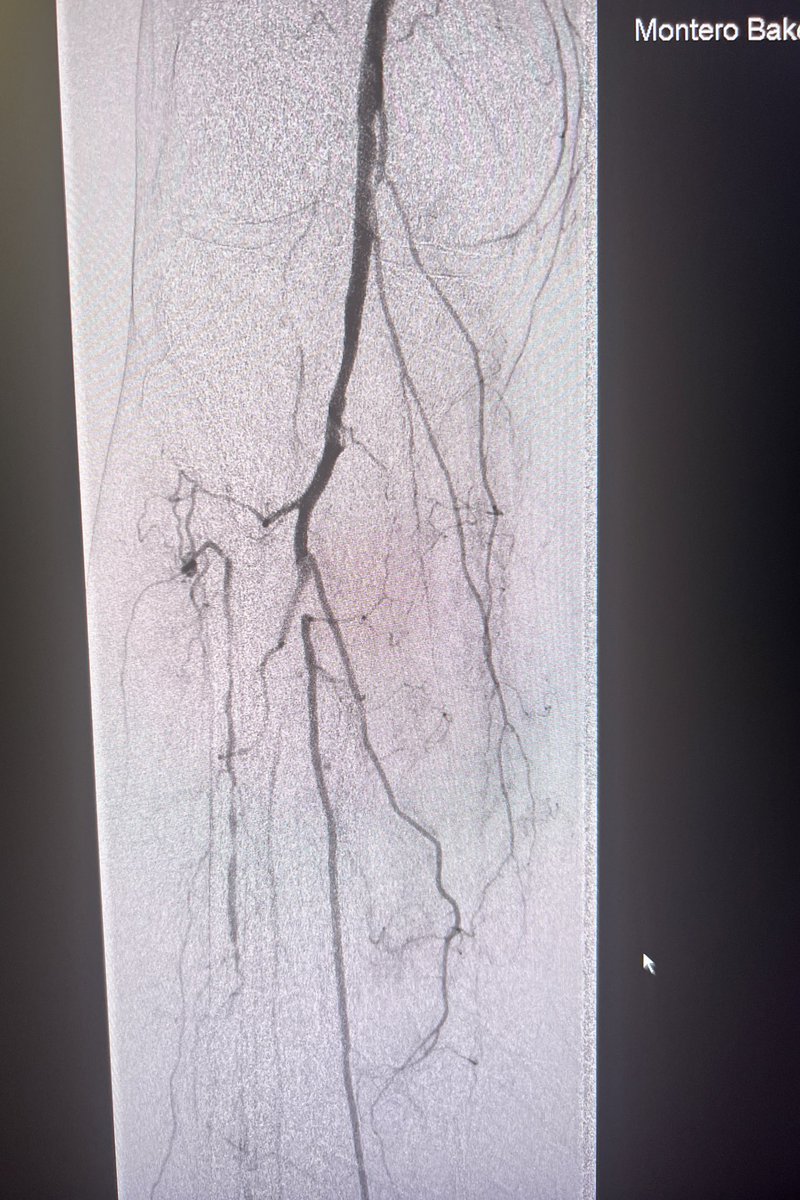

Curious if #CLIFighters feel there is a relationship between revasc of lower extremities and amputation in any center?